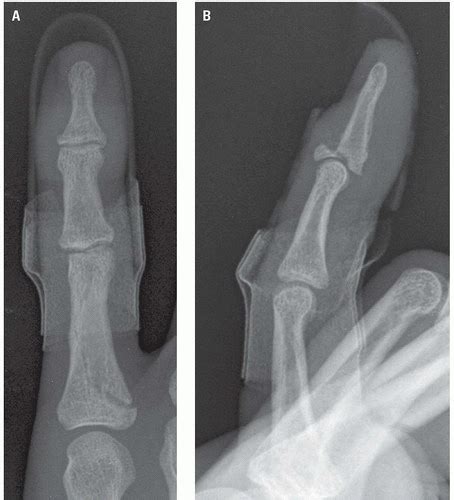

He experiences immediate pain and swelling about the base of his right thumb.

The most common pattern is extraarticular epibasal fracture. Subscribe to codify and get the code details in a flash. Some of the most notable changes include new codes related to orbital wall fractures, eye exams and neurostimulators. A patient is admitted with cellulitis and abscess of the left details: Learn how to perfectly code icd 10 codes for pathological fractures and how to differentiate them from traumatic fractures in coding injury reports. M84 disorder of continuity of bone. Building a fairer, healthier world. Coders will need very specific information in order to code for fractures. 80% of thumb fractures involve the metacarpal base. Septic shock is combined into code r65.21. Icd10 code for distal right fibula fracture. Unfortunately, most physicians don't call a fracture pathologic unless it is caused by a malignancy, gold says. Much more descriptive of the injury allowing for reflection of. Learn more about our commitment to ensuring that everyone, everywhere, can realize the right to good health. These code changes apply now through september 30, 2020. To code a diagnosis of this type, you must use one of the six child codes of s62.51 that describes the diagnosis 'fracture of proximal phalanx of thumb' in more detail. Not all pathologic fractures are due to cancer.